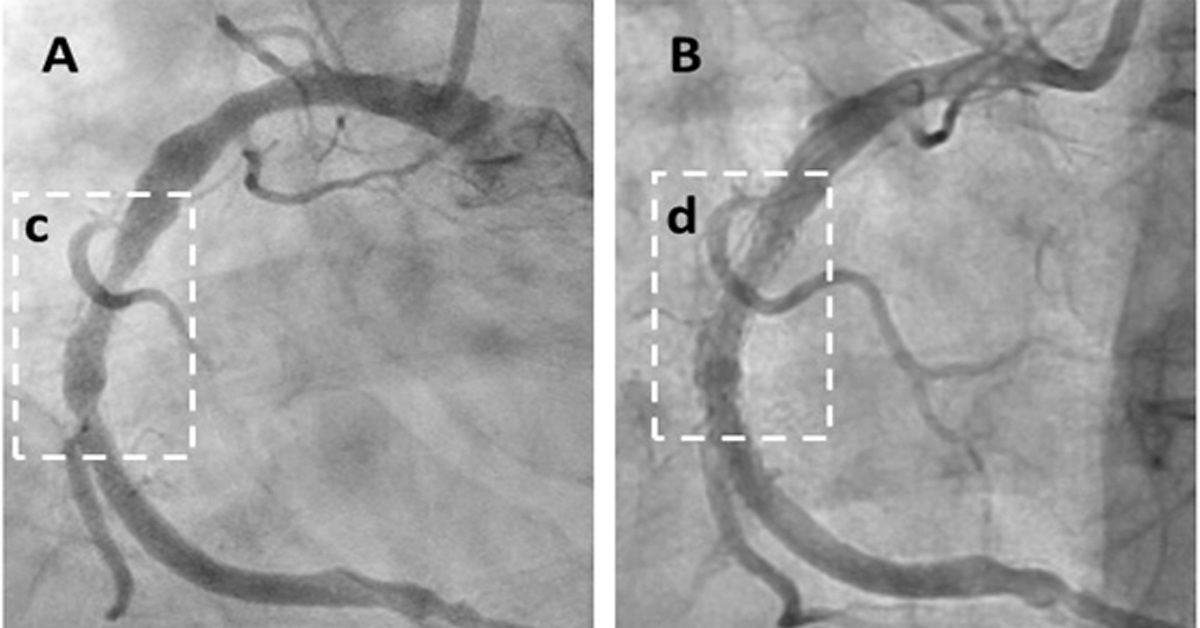

Angiogram: Plaque Reduced Within 6 Weeks

The peer-reviewed case series demonstrates rapid symptom relief and significant regression of arterial plaque, marking a potential paradigm shift in heart disease treatment. The study followed 20 high-risk patients with advanced angina, with 18 (90%) reporting substantial symptom improvement (P0.0001) compared to expected outcomes. Objective imaging confirmed unprecedented results, including Coronary Artery Calcium (CAC) score reductions (e.g., from 591 to 521) and a 70% coronary artery blockage reduced to 27%. Cavadex, formulated with 2-hydroxypropyl-β-cyclodextrin (HPβCD), stimulates the body's natural vascular repair, offering a faster, more effective approach than existing therapies.